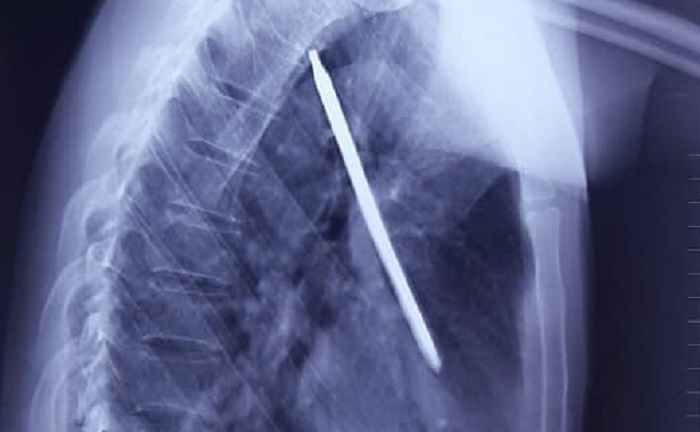

Cắt cỏ bằng máy, người đàn ông bị tuốc nơ vít cắm sâu vào phổi

Đang cắt cỏ bằng máy cắt cầm tay, anh N. bị chiếc tuốc nơ vít dài gần 20cm văng lên đâm thẳng vào ngực trái, nằm trọn trong phổi.